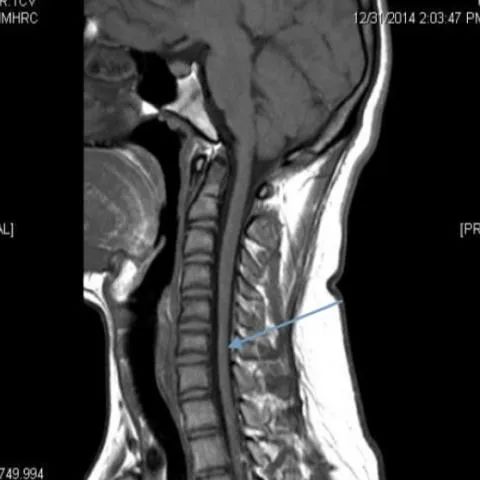

颈椎核磁共振在这种罕见疾病的诊断中起着重要的作用。矢状位磁共振成像显示细微的局灶性颈髓萎缩(图2 & 3),尤其是在下颈部。屈曲位成像示硬脑膜的前移位,后硬膜外腔增宽(图4)和更明显的脊髓变细,这在中立位不明显(图5)。

平山病是一种青少年型脊髓性肌萎缩症,其特征是手和前臂肌肉(C7-T1肌节)的单侧或不对称双侧受累。这种非进行性局灶性肌萎缩主要影响生命第二个十年的男性。感觉系统和肱桡肌的相对保留是这种肌萎缩的特征。虽然确切的机制尚不确定,但一些人认为脊柱和椎管内容物的不相称增长是短而紧的硬膜囊的原因,导致屈曲时脊髓受压。这一慢性过程导致脊髓前动脉区域的微循环障碍。中立位的MRI发现包括颈椎前凸丧失、局部脊髓变细或变平以及极少的髓内信号变化。屈曲位成像显示硬脑膜向前移位,导致后部硬膜外腔扩大。对比磁共振成像显示新月形强化硬膜外腔。颈椎在中立位和屈曲位的动态磁共振成像在诊断中是很重要的,尤其是在有典型临床表现的患者中。早期诊断是必不可少的,因为早期应用颈圈可以降低这种疾病的发病率。